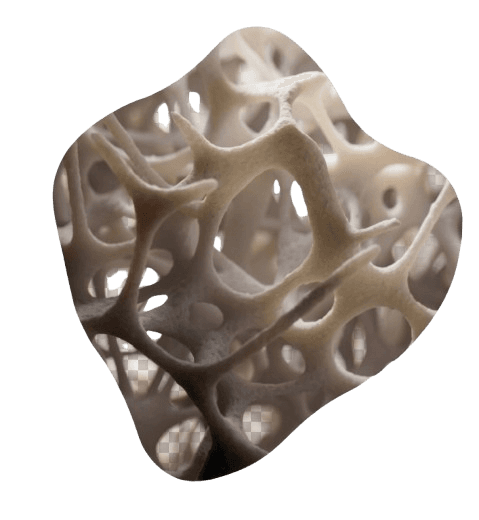

More Than Just Density

REMS assesses both bone mineral density and bone quality, giving a more complete and clinically meaningful picture of your skeletal health.

Clinically Validated

Published research shows REMS to be at least as accurate as DEXA and in some measures more precise, particularly when assessing the quality of bone tissue.

Understanding bone density at every level